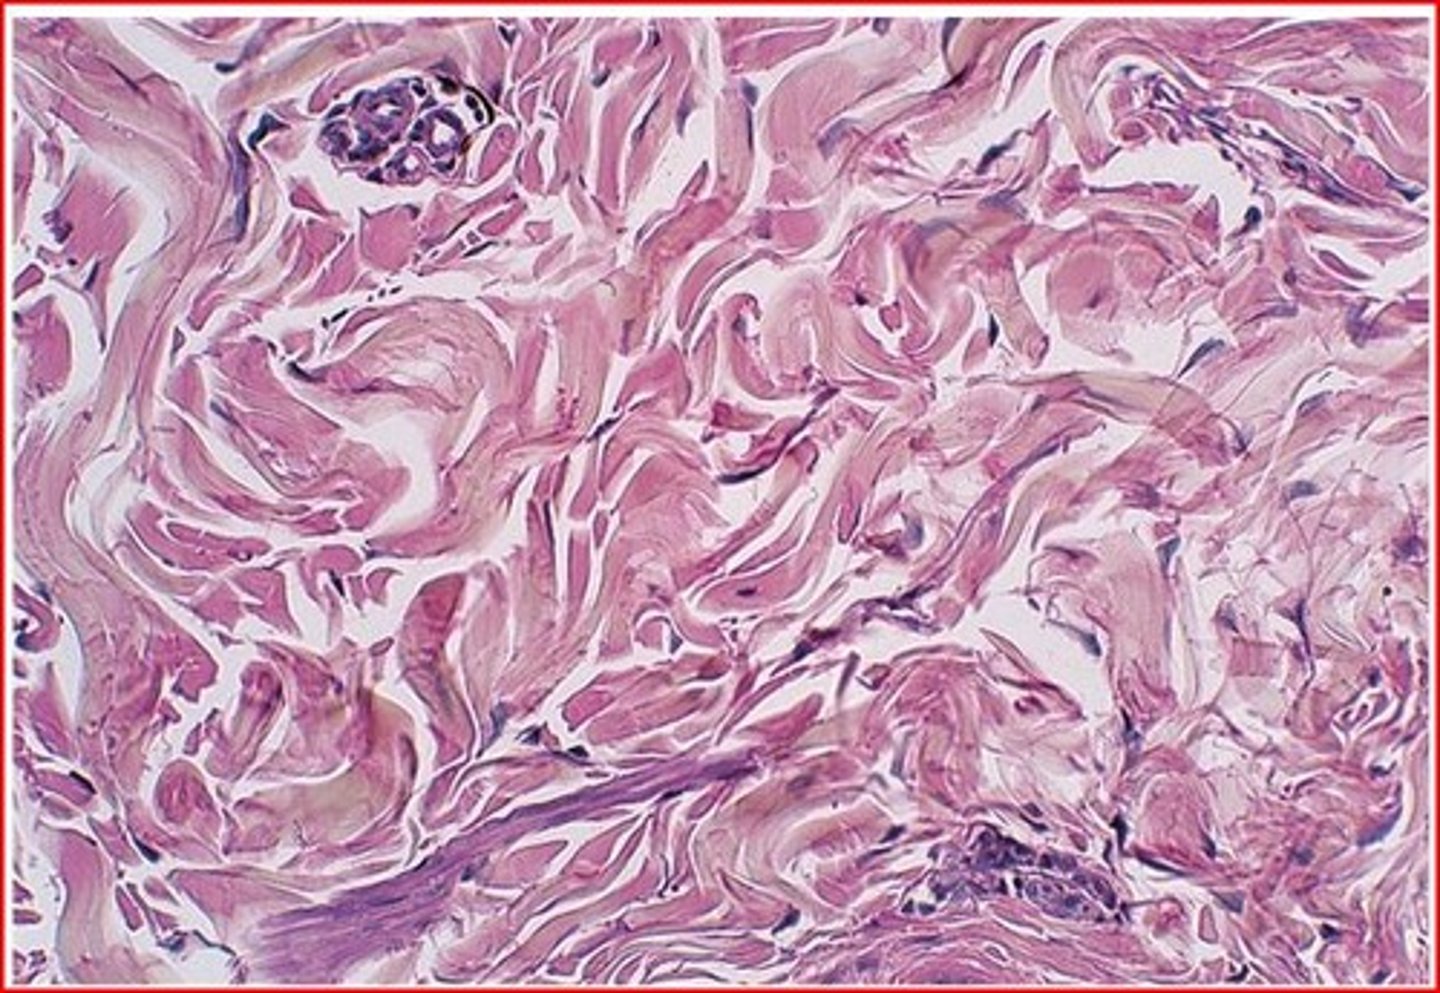

Dense Irregular Connective Tissue (CT)

Makes up the reticular layer of the dermis. Contains collagen and elastic fibers for strength and flexibility.

The second major skin region, is strong flexible connective tissue. Its cells are fibroblast, macrophages and occasional mast cells. Richly supplied with nerve fibers, blood vessels, and lymphatic vessels. Has two layers, papillary and reticular layers

Reticular Layer

Accounts for 80% of the thickness of the dermis, it is coarse, irregularly arranged, and dense fibrous connective tissue. Collagen fibers provide strength and resiliency, Elastic fibers provide stretch-recoil properties.